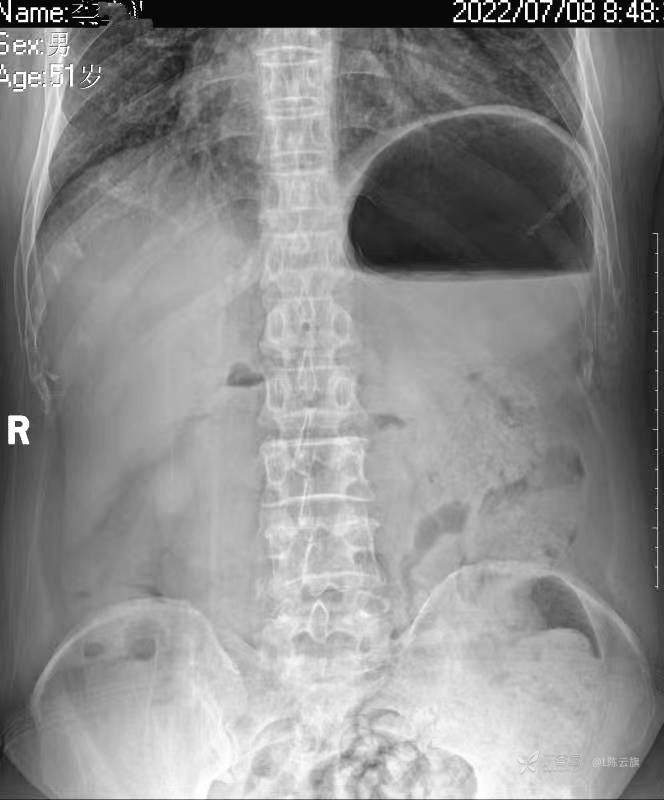

华夏览雄 达人已点赞1、患者男,51岁,精神病长期住院患者,主要病史只有时不时觉得腹部不适,其他不详。系列胸片为定期胸部检查。

2、第一张腹部立位片是个腹部病变的典型平片表现,你能明确诊断吗?